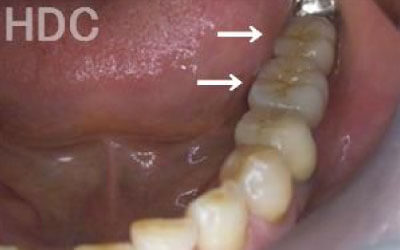

しばらくすると抜けたままでも慣れてきますが、大きな問題が発生します。

1 周囲の歯が早く抜ける

抜けた歯に掛かるはずだった噛むときの力は、気が付かずに別の歯が負担しています。 それにより残っている歯が突然折れて抜歯になることはよくあります。

ブリッジでも入れ歯でも、他の歯に負担がかかって歯が連鎖して抜歯になっていく現象が起こります。

ただインプラントは、周囲の歯に負担がかかることは一切無く、残っている歯に一番優しい治療です。